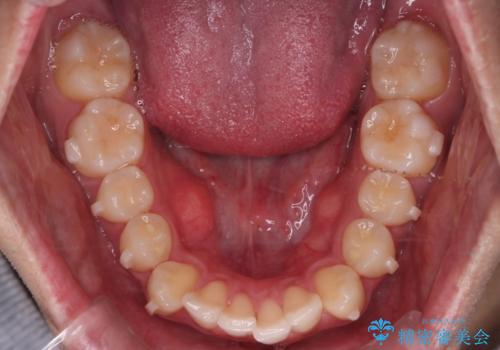

患者様よりシュミレーション通りに歯が動くか心配との事だったので

出来るだけ計画通りに歯を動かすために、マウスピース1枚あたりの使用時間を長めに使っていただきました。

そのため、多少治療期間が延びましたが、リファイメント(マウスピースの再発注)なしで終了することができました。